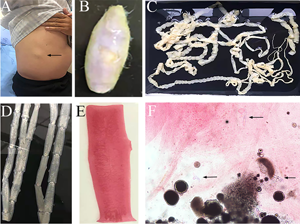

The routine laboratory blood tests, including eosinophil and lymphocyte count, were completely normal apart from the elevated inflammation markers (C-reactive protein and neutrophil count). Schistosomes, Clonorchis sinensis, Echinococcus granulosus and Toxoplasma gondii antibodies were negative in his serum, as were Cryptococcus capsular antigen and next-generation sequencing results from cerebrospinal fluid. Multiple intracranial nodules affecting the supratentorial and infratentorial cerebral parenchyma were shown in detail on CT and MRI of the head, indicating possible intracranial parasitic infection (Fig. 1). Ultrasound scan confirmed the presence of 2 palpable and soft masses located in muscles, which were approximately 19 × 8 × 15 mm3 under the right chest wall and 26 × 10 × 19 mm3 under the right midaxillary line (Fig. 2). A subsequent biopsy of the mass (Fig. 3) showed larval-like tissue, peripheral fibrous tissue hyperplasia, lymphocytic infiltration and hyaline degeneration. The patient was probably diagnosed with taeniasis and cysticercosis and treated with oral albendazole (400 mg, twice daily) over 2 weeks. Hydrocortisone 50 mg was provided 2 days after the first albendazole treatment to counteract any potential negative effects on the central nervous system. After only 2 days of this antiparasitic treatment, the adult tapeworm was eliminated through the patient's feces (Fig. 3). When compared with the first MRI (half a month before antiparasitic treatment), the second MRI (half a month after antiparasitic treatment) demonstrated a slightly smaller focus (Fig. 1). The headache and vomiting resolved, and the patient remained symptom free over a 3-month follow-up period.

Fig. 1. MRI shows that the largest cystic nodule was located next to the left ventricular triangle: (A–C) half a month before antiparasitic treatment and (D–F) half a month after antiparasitic treatment.